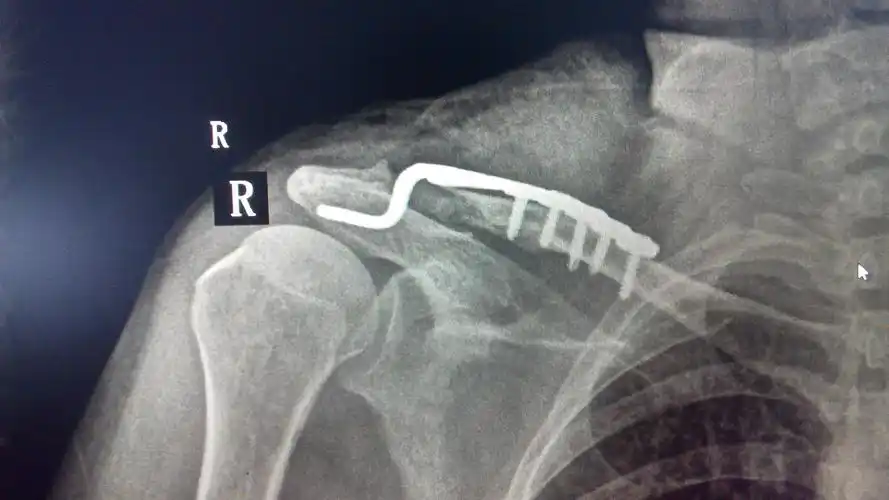

锁骨肩峰端骨折钩板固定